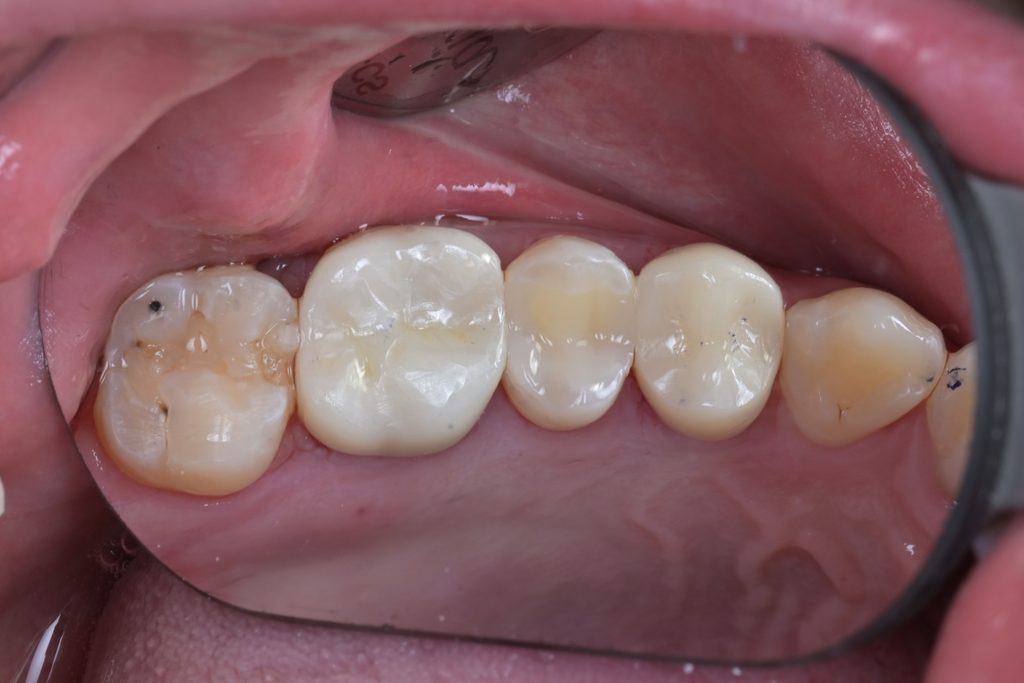

치료 후 최종 마무리 및 결과

레진빌드업 완료 후, 교합지를 이용하여 반대편 치아와의 교합 접촉을 세밀하게 조정하고, 다이아몬드 버와 폴리싱 시스템을 사용하여 최종 연마를 진행했습니다.

[사진14: 협측면에서 본 최종 치